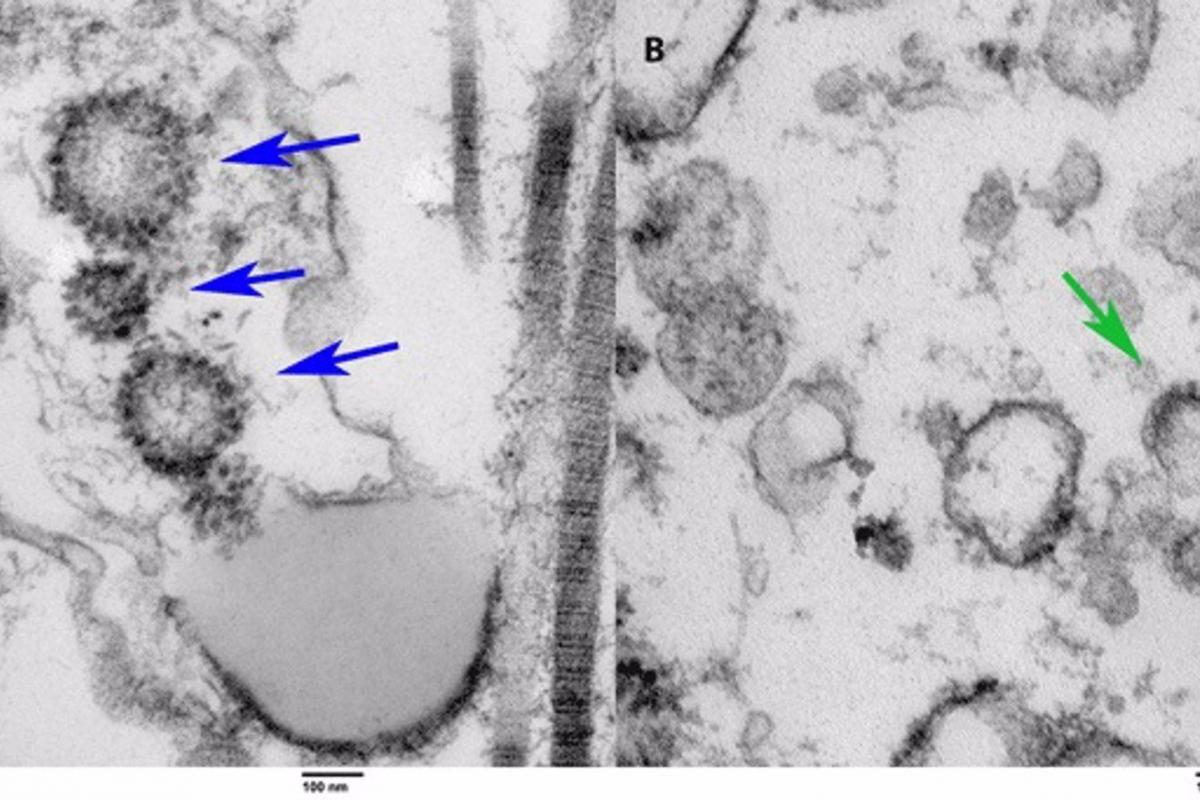

A la izquierda, el tejido de un paciente vivo previamente COVID positivo. A la derecha, el tejido recogido por autopsia de una persona que murió de COVID. Las flechas apuntan a las partículas virales de COVID en ambos espec&ia...UNIVERSITY OF MIAMI MILLER SCHOOL OF MEDICINE

Los investigadores analizaron el tejido testicular de las autopsias de seis hombres que murieron de la infección por COVID-19. Encontraron alteraciones en la función espermática en tres de las muestras de testículos y evidencia del virus usando microscopía electrónica en el tejido de uno de ellos.

“También identificamos la presencia del virus en un hombre que se sometió a una biopsia de testículo para la infertilidad, pero que tenía antecedentes de COVID-19. Así que el paciente dio negativo y estaba asintomático después de tener COVID-19 pero aún así mostraba la presencia del virus dentro de los testículos. Esta es la primera investigación publicada que informa sobre el caso de un paciente vivo que se recuperó del virus con presencia de COVID-19. El hallazgo es novedoso, notable, y ciertamente digno de una mayor exploración”, apunta Ramasamy.